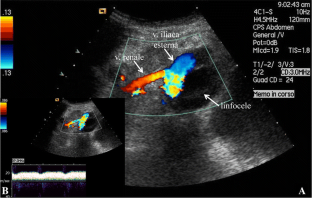

Fig. 4